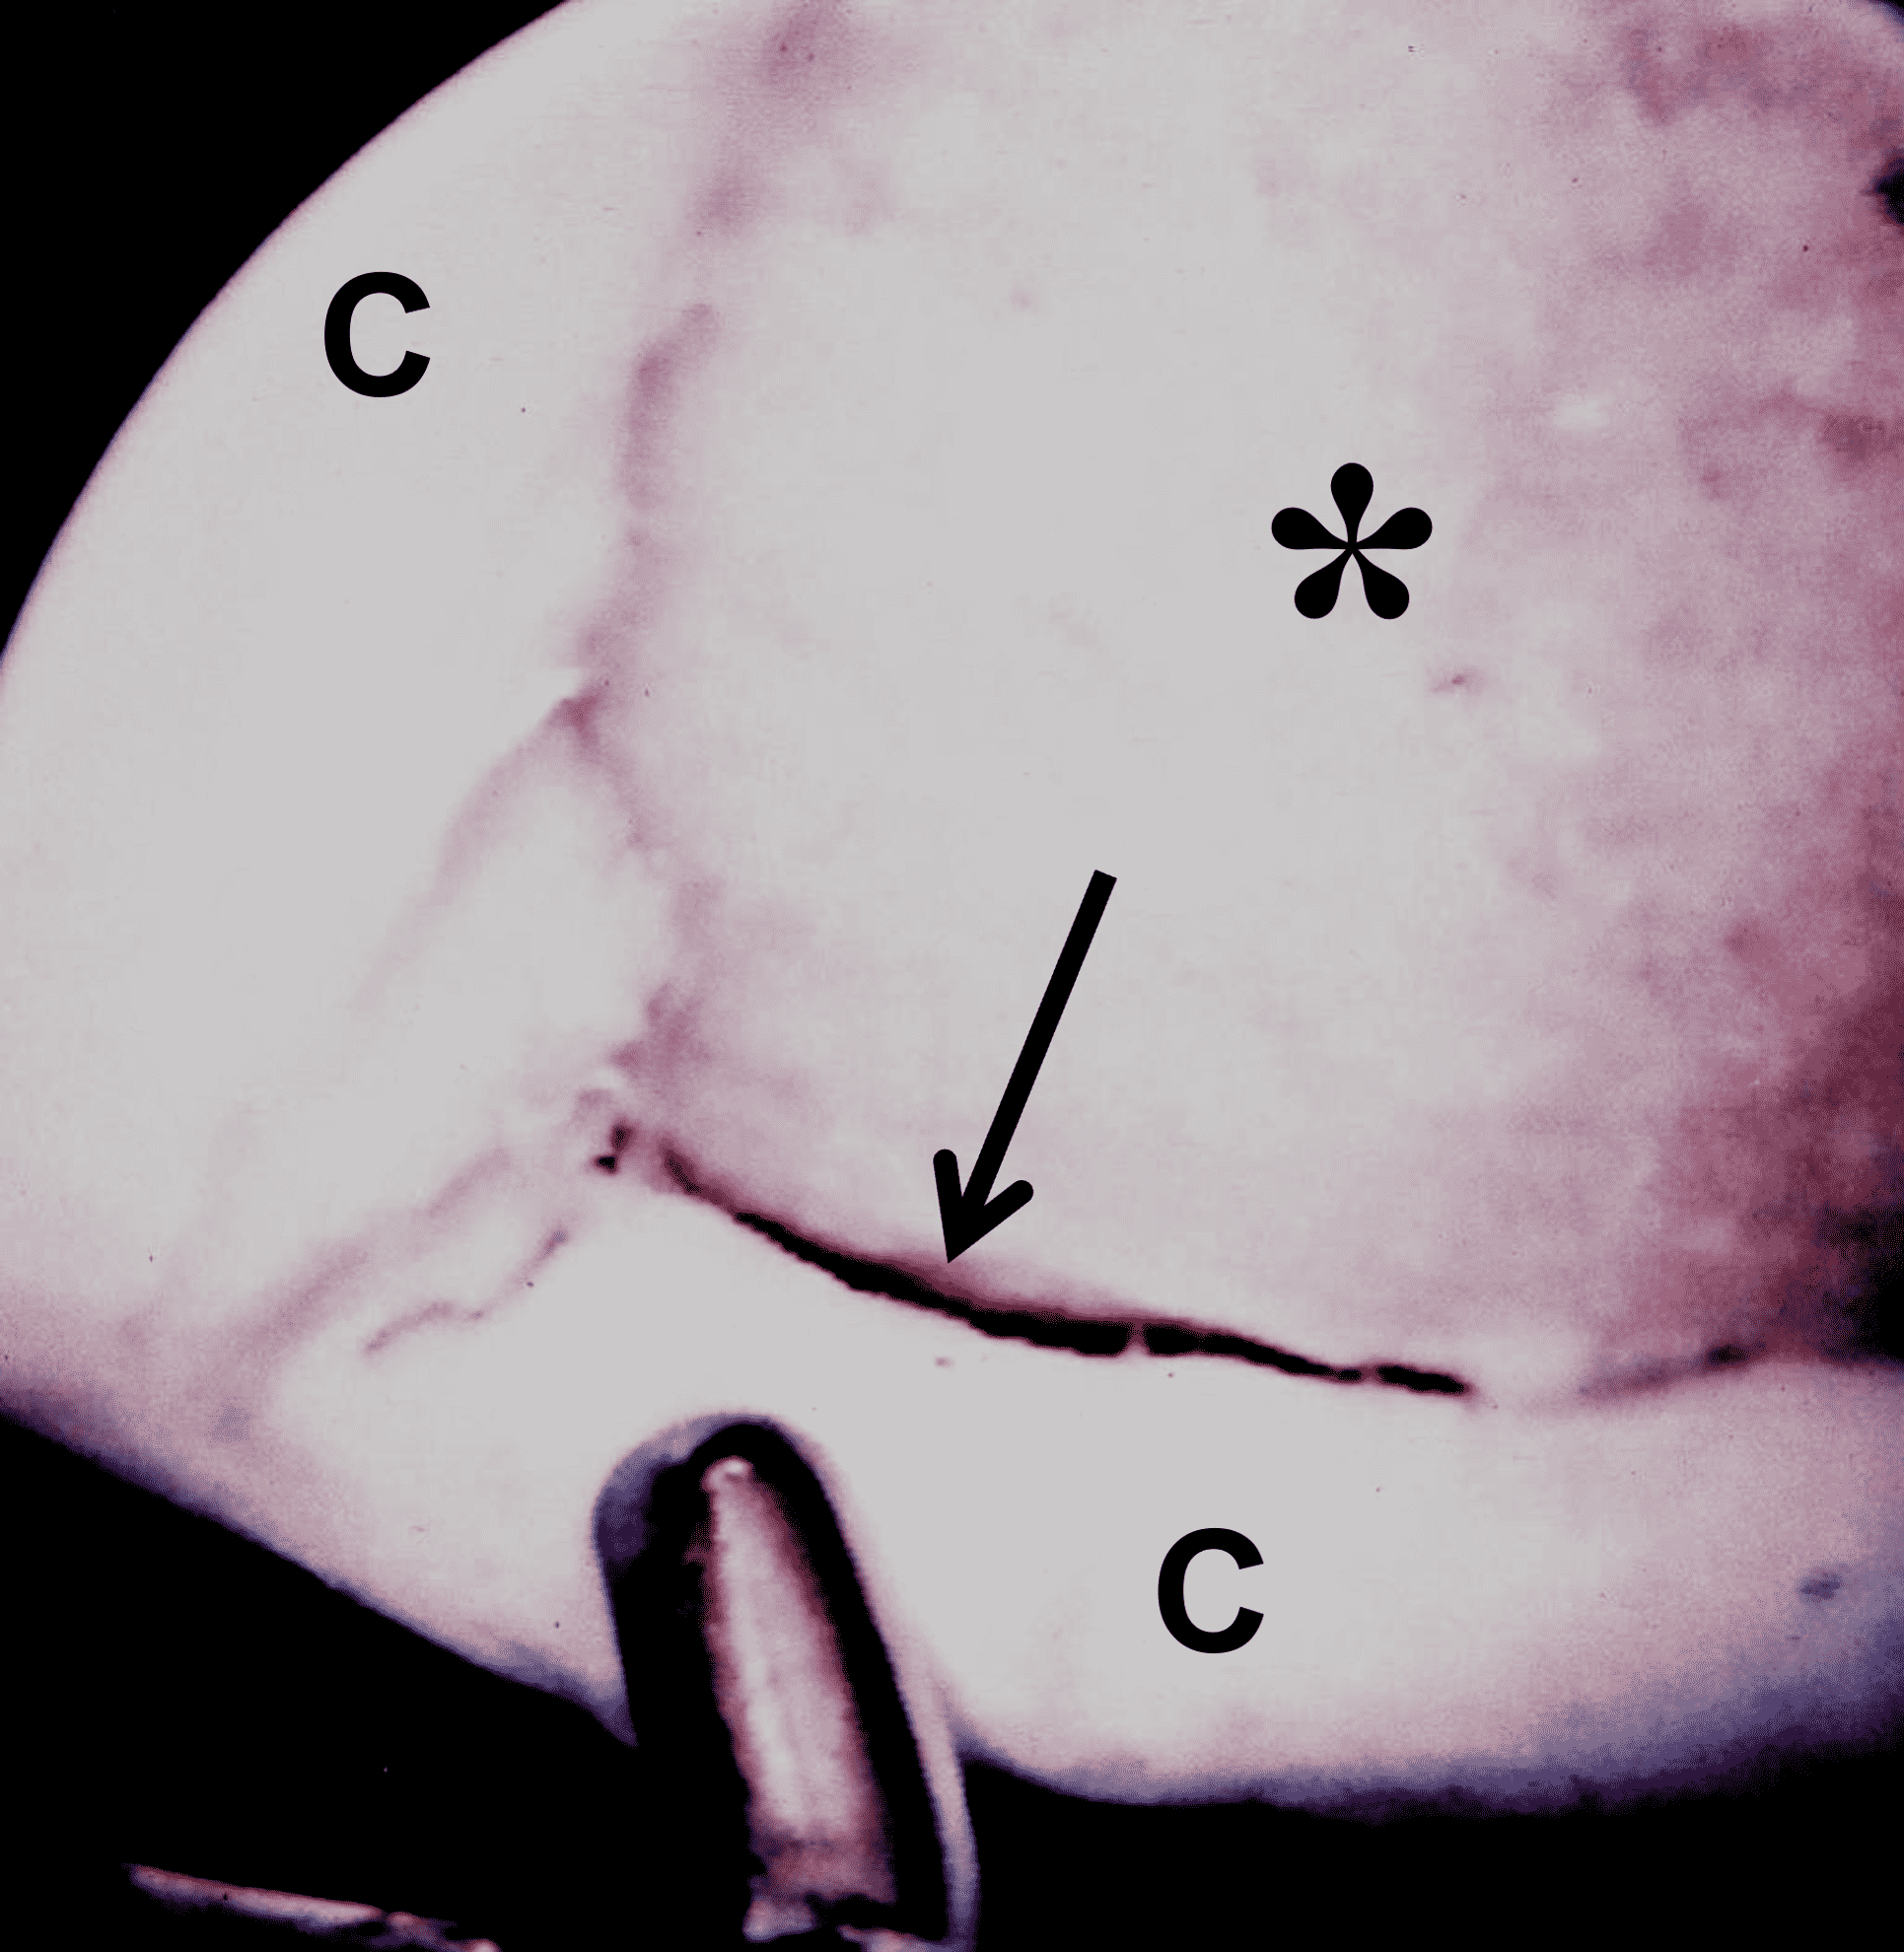

Articular cartilage is susceptible to both traumatic and degenerative lesions, but restoration procedures work best for traumatic lesions. Direct impaction, shear, and twisting mechanisms can injure the articular cartilage.3 Traumatic lesions include chondral fractures, which have a characteristic appearance on MRI characterized by a sharp transition between the lesion and surrounding normal cartilage with the walls of the defect oriented perpendicular to the articular surface (Figures 3A and 3B). Defects are often full thickness, extending to the subchondral bone plate. Subchondral marrow edema is common.4 An unstable cartilage fragment may be present in the crater or displaced as a loose body in the joint. Chondral flaps appear similar to chondral fractures but remain attached to the surrounding cartilage along one side of the lesion, which can act as a hinged trap door (Figures 3C and 3D). The two types of traumatic lesion often coexist, with a chondral fracture frequently demonstrating unstable flap(s) in its periphery (Figures 3E and 3F).

Figure 3: Examples of cartilage injuries amenable to restoration procedures. (3A) Drawing and (3B) sagittal fat-suppressed fluid-sensitive image showing a chondral fracture with vertical walls perpendicular to the articular surface (arrows), sharply demarcating the crater from the surrounding normal cartilage, and focal subchondral marrow edema (asterisk). (3C) Drawing and (3D) axial fat-suppressed fluid-sensitive image showing a chondral flap with a vertical wall on one side of the lesion (red arrow) and a intact, hinged bridge of cartilage on the other, with a full-thickness defect in between (yellow arrow). (3E) Sagittal T2-weighted image of a combined chondral fracture and flap. The chondral fracture has sharp margins (yellow arrows) with the surrounding intact cartilage, while a delaminating flap (black arrow) is present along the posterior lesion margin. (3F) Corresponding arthroscopic picture. The subchondral bone plate is exposed at the base of the lesion (asterisk), with a delaminating flap in the lesion periphery (arrow). C = normal surrounding cartilage.